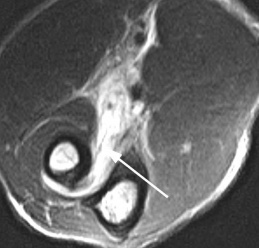

Рентгенограмма (слева) и МРТ локтевого сустава (справа). Суставная мышь (стрелка). Выпот и синовит на Т2-взвешенной МРТ.

На МРТ локтевого сустава при любом переломе видна реакция костного мозга. Это помогает в диагностике, если перелом сразу не виден на рентгенограмме. В дальнейшем можно прицельно дообследовать подозрительную область. При консолидировавшихся переломах на МРТ остается видна линия перелома, а окружающий костный мозг нередко подвергается жировой дегенерации. МРТ в СПб стало необходимым компонентом обследования пациентов с травмой суставов и осуществимо в высоких полях или открытом МРТ. МРТ СПб дает возможность исследовать методом МРТ локтевой сустав в разных центрах, однако, наш опыт позволяет рекомендовать обследование именно у нас.